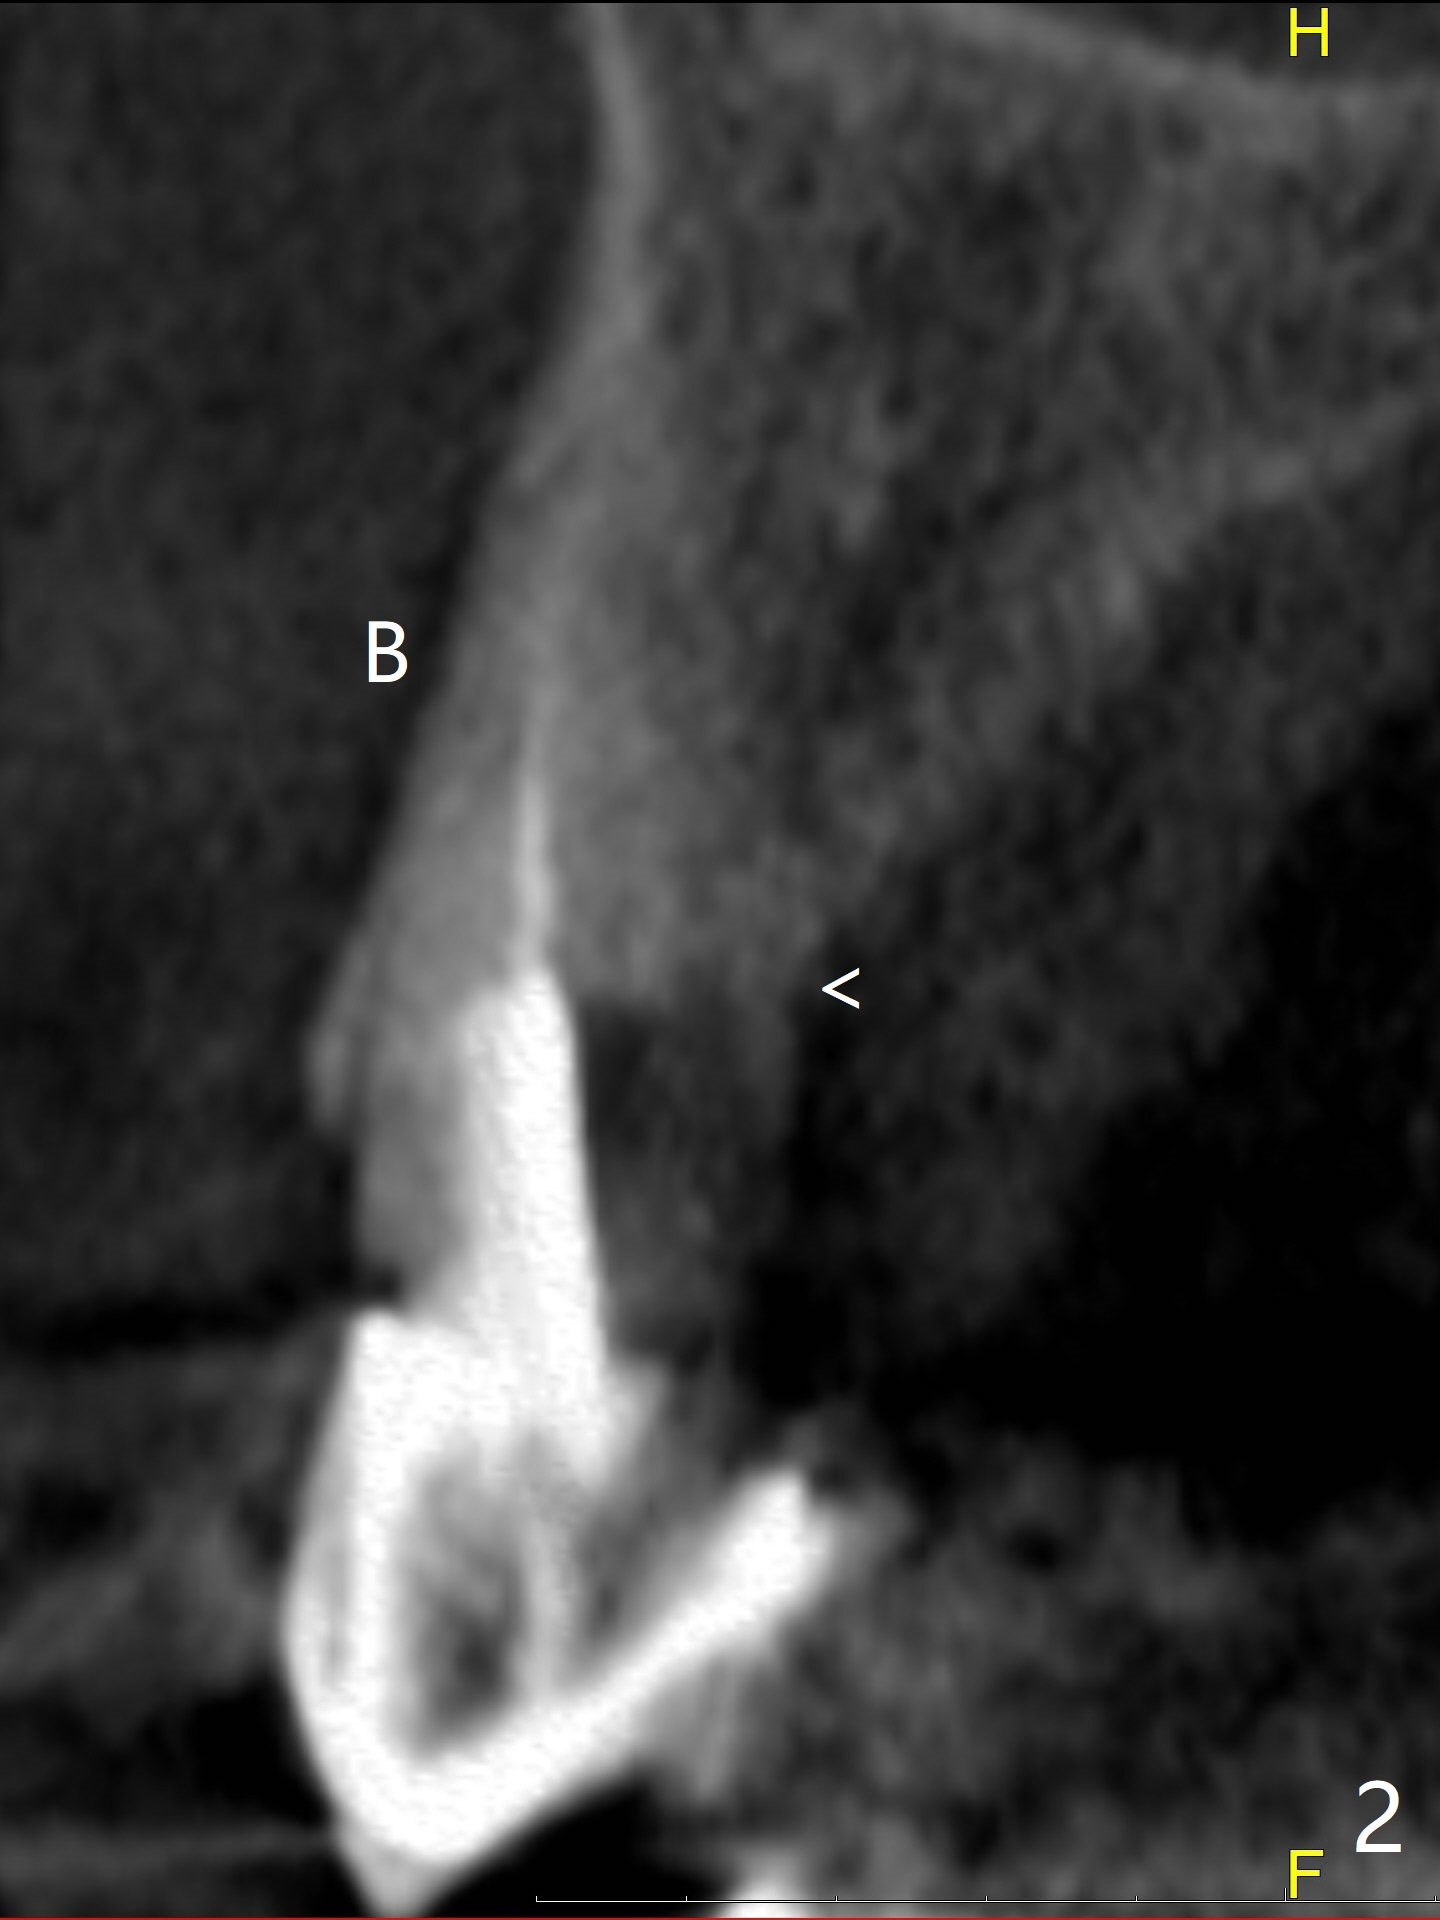

A 90-year-old petit woman fractures the tooth #6 equigingival 5 years 5 months post cementation of #7 crown (Fig.1). Since the palatal crest is high (Fig.2 <), the implant should not be too long (Fig.3, IS Mini-implant). Sticky bone if possible. Undrill considering osteoporosis. Return to Protect Graft No Antibiotic 10 Xin Wei, DDS, PhD, MS 1st edition 07/10/2021, last revision 08/08/2021